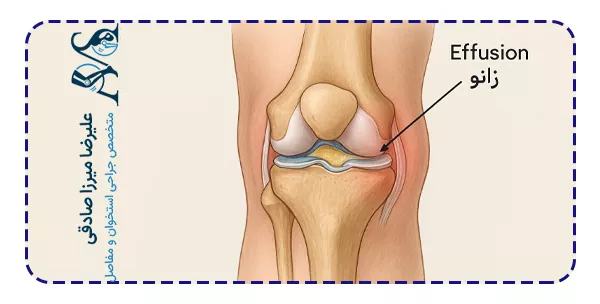

افیوژن زانو اصطلاحی است که در پزشکی برای توصیف تجمع غیرطبیعی مایع در مفصل زانو استفاده میشود. این وضعیت نهتنها باعث تورم و درد میشود، بلکه میتواند حرکت مفصل را نیز محدود کند. در شرایط طبیعی، در مفصل زانو مقدار کمی مایع سینوویال وجود دارد که وظیفه روانسازی و تغذیه غضروفها را بر عهده دارد. اما زمانی که التهاب، ضربه یا عفونت رخ میدهد، میزان این مایع افزایش یافته و باعث تورم زانو میشود.

افیوژن زانو یا همان “آب آوردن زانو”، وضعیتی است که در آن مایع اضافی درون یا اطراف مفصل زانو جمع میشود. این مایع میتواند شامل مایع سینوویال، خون یا چرک باشد که بسته به نوع آسیب یا بیماری، ترکیب متفاوتی دارد. در واقع این مایع نشانهای از وجود التهاب یا واکنش بدن به آسیب است.

در مفصل سالم، میزان مایع بسیار کم است و بین استخوانها حرکت را تسهیل میکند. اما زمانی که مفصل تحریک میشود، سلولهای پوشاننده آن مایع بیشتری تولید میکنند. این تجمع بیش از حد، موجب ورم، احساس سنگینی و در برخی موارد محدودیت حرکتی میشود.